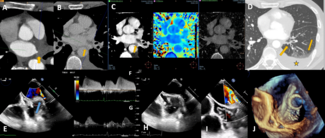

A 64-year-old woman presented with acute onset left-sided facial droop, left upper extremity paresis, and aphasia. Magnetic resonance imaging demonstrated acute infarction of the right thalamus.